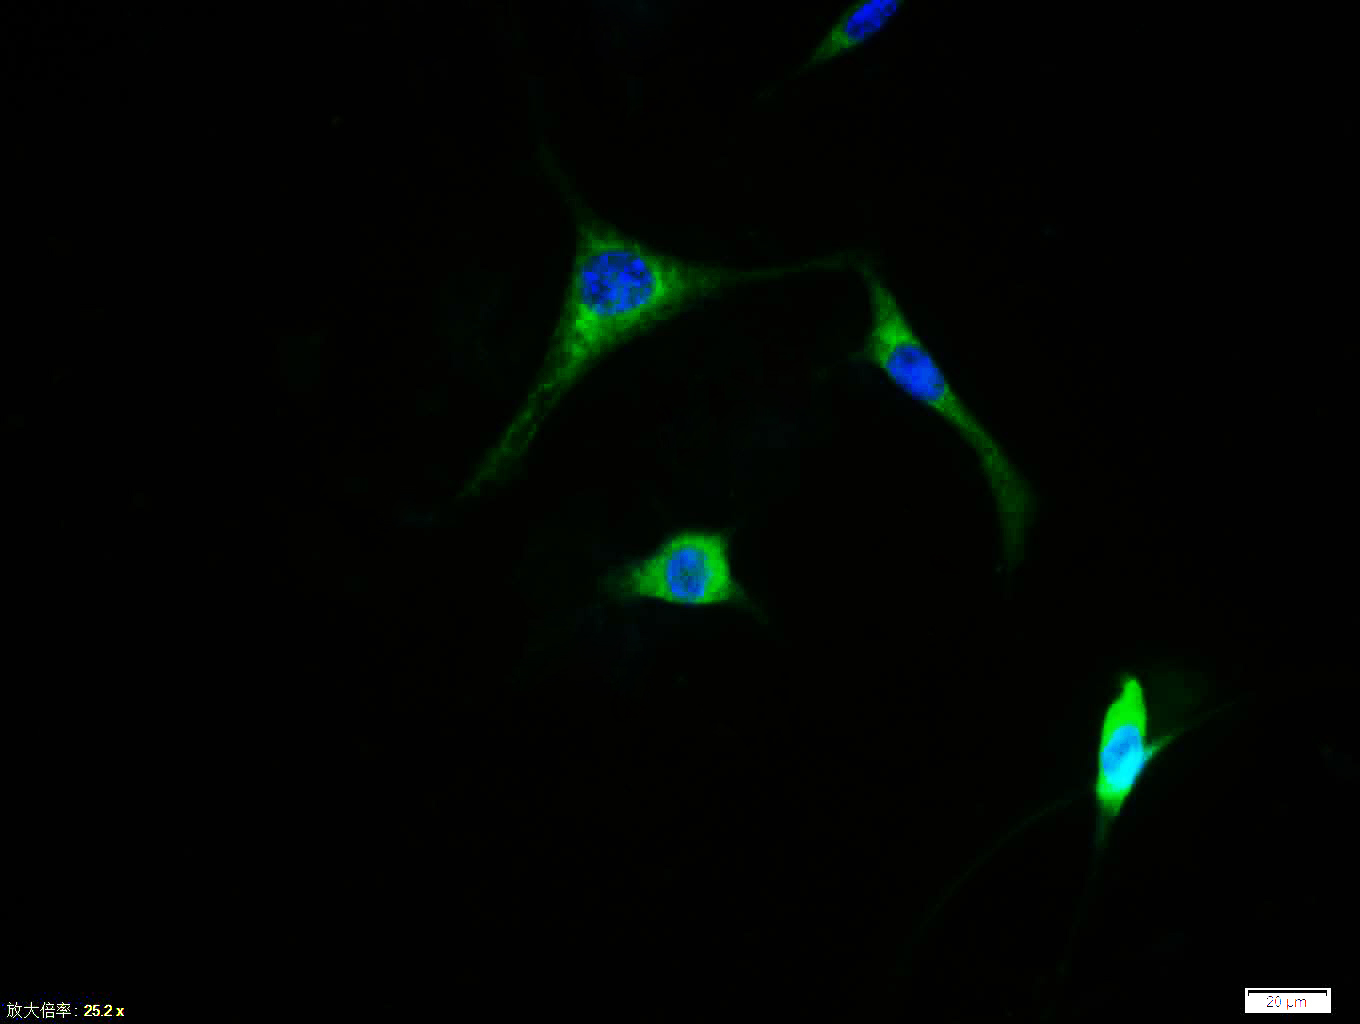

Tissue/cell:MCF7 cell; 4% Paraformaldehyde-fixed; Triton X-100 at room temperature for 20 min; Blocking buffer (normal goat serum, C-0005) at 37°C for 20 min; Antibody incubation with (c-fos) polyclonal Antibody, Unconjugated (bs-0469R) 1:100, 90 minutes at 37°C; followed by a FITC conjugated Goat Anti-Rabbit IgG antibody at 37°C for 90 minutes, DAPI (blue, C02-04002) was used to stain the cell nuclei.

Tissue/cell: A431 cell; 4% Paraformaldehyde-fixed; Triton X-100 at room temperature for 20 min; Blocking buffer (normal goat serum, C-0005) at 37°C for 20 min; Antibody incubation with (c-fos) polyclonal Antibody, Unconjugated (bs-0469R) 1:100, 90 minutes at 37°C; followed by a FITC conjugated Goat Anti-Rabbit IgG antibody at 37°C for 90 minutes, DAPI (blue, C02-04002) was used to stain the cell nuclei.